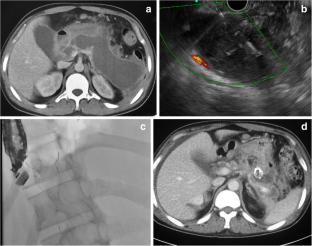

Fig. 2